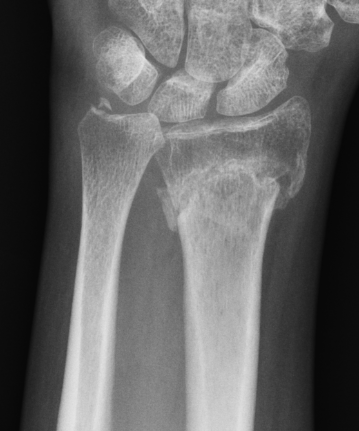

Xray

Bilateral xrays

PA film in neutral

- wrist neutral

- elbow & shoulder at 90°

CT